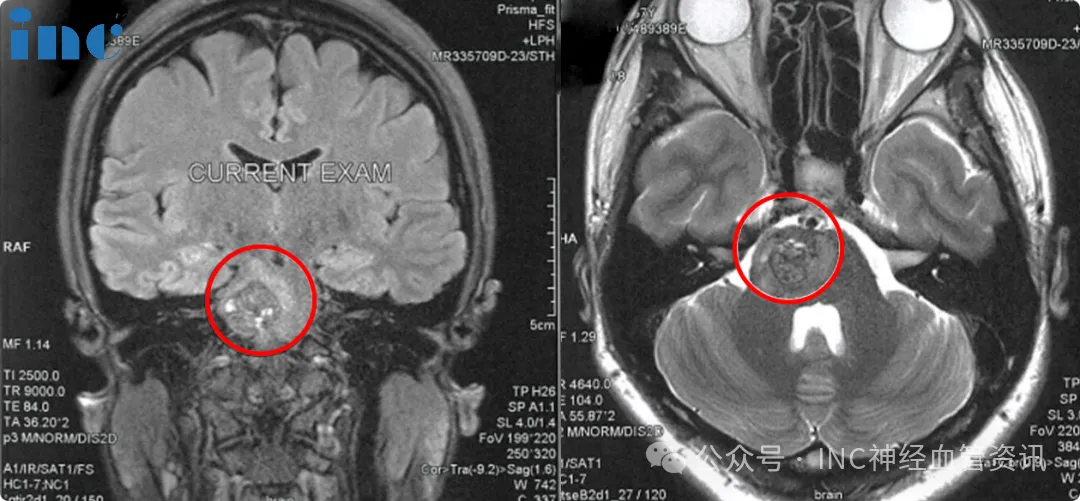

术后2年,佩珊早已回归正常生活,最新一次复查MRI结果提示那颗病灶已被完全切除,今后不会再引起任何出血,佩珊不必再有担忧。

佩珊最新的复查影像,是这场高难度战役最终胜利的无声宣言。那个曾经连推门都害怕的女士,如今已彻底摆脱阴影,拥抱她本就该拥有的、充满活力的正常生活。